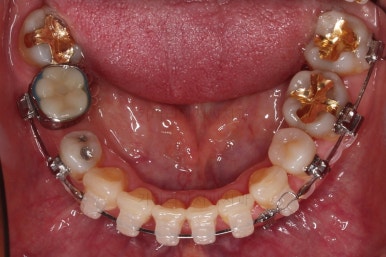

아랫니가 윗니보다 더 많이 삐뚤어 있는데요.

적절한 시점에 유치를 뽑아내고 남은 공간을 줄여나갑니다.

아래쪽 임플란트는 움직이지 않기 때문에 해당 치아를 기준으로 다른 치아를 모두 셋팅해야 하는 매우 난이도 높은 치료가 진행되었습니다.

임플란트는 크기가 작았으므로 교합을 위해서는 어쩔 수 없이 해당 부위에 틈이 남을 수 밖에 없었고요.

남은 틈은 임플란트 상부 보철을 재제작하면서 조절을 하기로 했습니다.

동래임플란트교정 마무리 되었습니다.

임플란트 머리도 잘 올라갔고, 치열도 가지런해졌으며 교합이나 중앙선도 적절히 마무리 되었습니다.